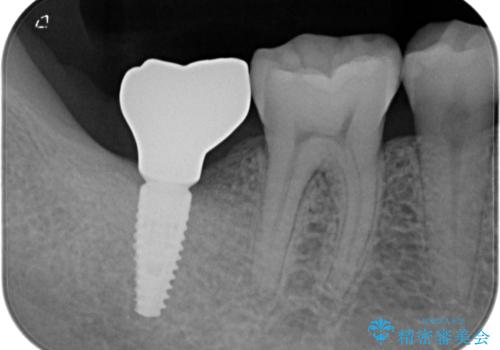

部分矯正で咬み合わせを改善 奥歯のインプラント治療

- 左下欠損部のインプラント治療を希望して来院された患者様です。

左下の欠損部を長期間欠損を放置していたことで、咬み合う上の奥歯が動いてしまっていたので、まずは上顎奥歯の部分矯正を行うこととしました。

理想的な咬み合わせに改善した上で、インプラント補綴治療を行うこととしました。

部分矯正を行ったこと治療期間は長くなりましたが、違和感のない咬み合わせを達成することができました。